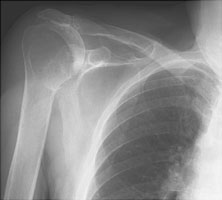

- Click on the image for a larger versionBAxillary radiograph of the shoulder. This view demonstrates the anterior dislocation of the humeral head (towards the coracoid).